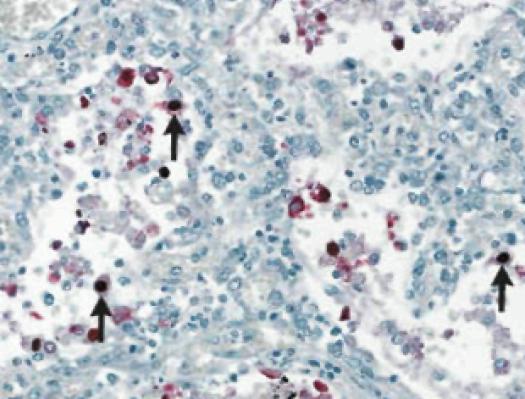

In fatal cases of H1N1 virus infection, the most consistent histopathological findings are varying degrees of diffuse alveolar damage, with hyaline membranes and septal edema, tracheitis, and necrotizing bronchiolitis (Figure 1). Other early changes include pulmonary vascular congestion and, in some cases, alveolar hemorrhage. In addition to infecting cells in the upper respiratory and tracheo-bronchial epithelium and mucosal glands, the 2009 H1N1 virus targets alveolar lining cells (type I and II pneumocytes) (Figure 2). Viral antigens have been readily detectable in about two-thirds of patients who died within 10 days after the onset of illness and may be detectable for more than 10 days.4Other autopsy findings include hemophagocytosis, pulmonary thromboemboli and hemorrhage, and myocarditis.23 Bronchopneumonia with evidence of bacterial co-infection has been found in 26-38% of fatal cases.27